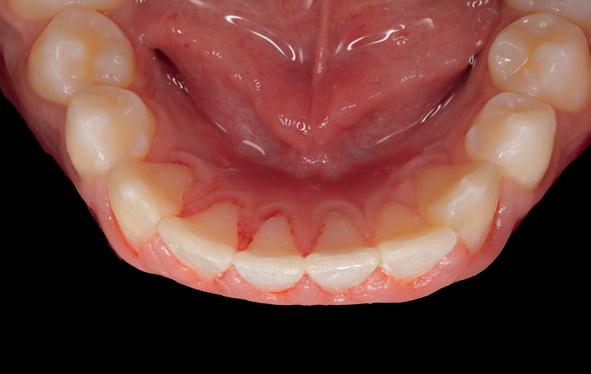

In het geval van een trauma is het altijd prettig om de oorzaak te weten en tegelijkertijd dit kort en bondig te houden, zodat het trauma snel behandeld kan worden. Dit kan vaak al aan de telefoon worden uitgevraagd en wanneer de patiënt in de stoel zit worden geverifieerd. In de algehele gezondheid bleek niets veranderd, behalve het opgelopen trauma: ASA I klasse. In het korte gesprek probeerde ik te achterhalen wat de patiënt zelf kon voelen en hij gaf aan last te hebben van de voortanden in de boven- en onderkaak alsmede moeite te hebben met de kiezen op elkaar te krijgen (afbeelding 1-4).

Niet alle testen zijn kort na trauma goed te onderzoeken, maar probeer toch zo veel mogelijk vast te leggen. Bij de toekomstige controles kan dit een grote rol spelen bij het stellen van een diagnose en het bepalen van eventuele vervolgbehandelingen. Hierbij gaat het doorgaans om pulpa- en peri-apicale diagnostiek. Voor een betrouwbare uitslag wordt geadviseerd de elementen meerdere malen en in willekeurige volgorde te testen. Uitkomsten klinisch onderzoek:

• 11, 21 verplaatsing naar binnen. 12 pulpa exponatie met fractuurlijn voorbij glazuur-cementgrens.

Onderlip 2 laceraties, alleen zwelling palpeerbaar.

• Patiënt komt niet in occlusie en vertoont een klasse 3 beet.

• Statische en dynamische testen hebben negatieve uitslag op pijn.